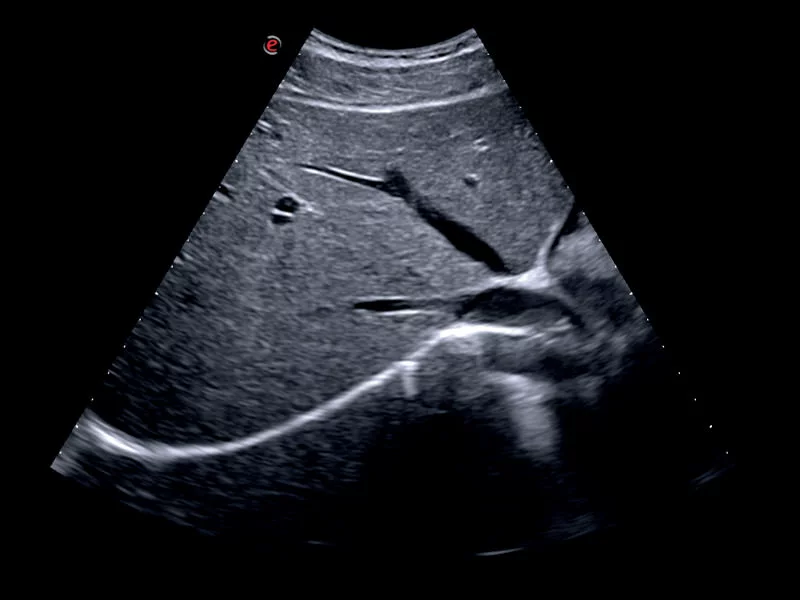

MyLab™X9 - Interventional

MyLab™X9 - Interventional